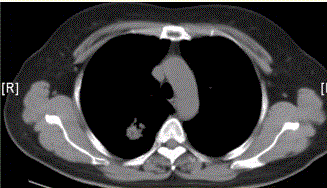

问题 患者女,54岁,无症状,常规体检透视时发现右上肺阴影。既往无结核病史。体格检查阴性。CT结果如下图。 易出现空洞的肺癌类型是

选项 A.鳞癌 B.腺癌 C.未分化癌 D.肺泡癌 E.转移性肿瘤 F.肺类癌

答案 A

解析 A